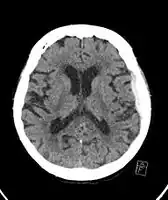

Subdural hematoma as marked by the arrow with significant midline shift

Chronic subdural after treatment with burr holes